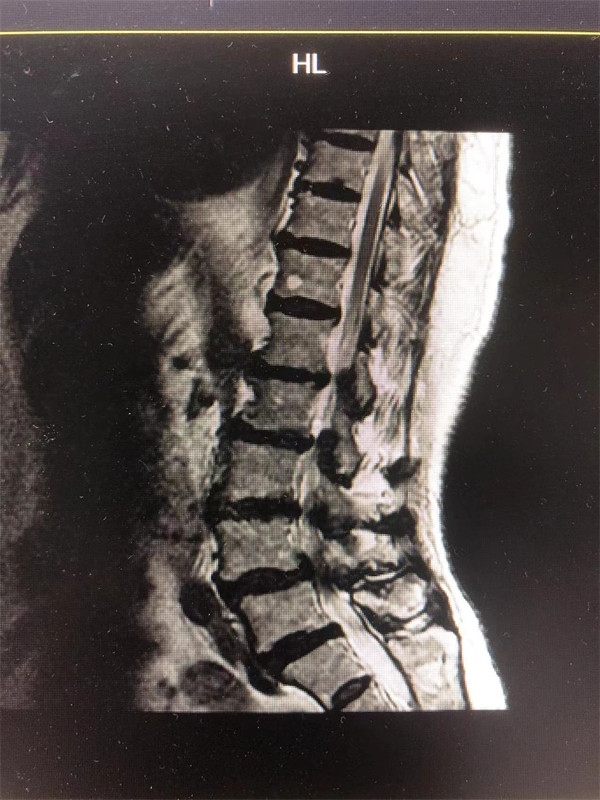

戈主任仔細詢問阿婆病情癥狀,綜合查體及MRI片情況,認為阿婆有明顯的腰椎滑脫,腰椎管狹窄,這是引發(fā)阿婆病痛的主要因素。

手術(shù)前↓